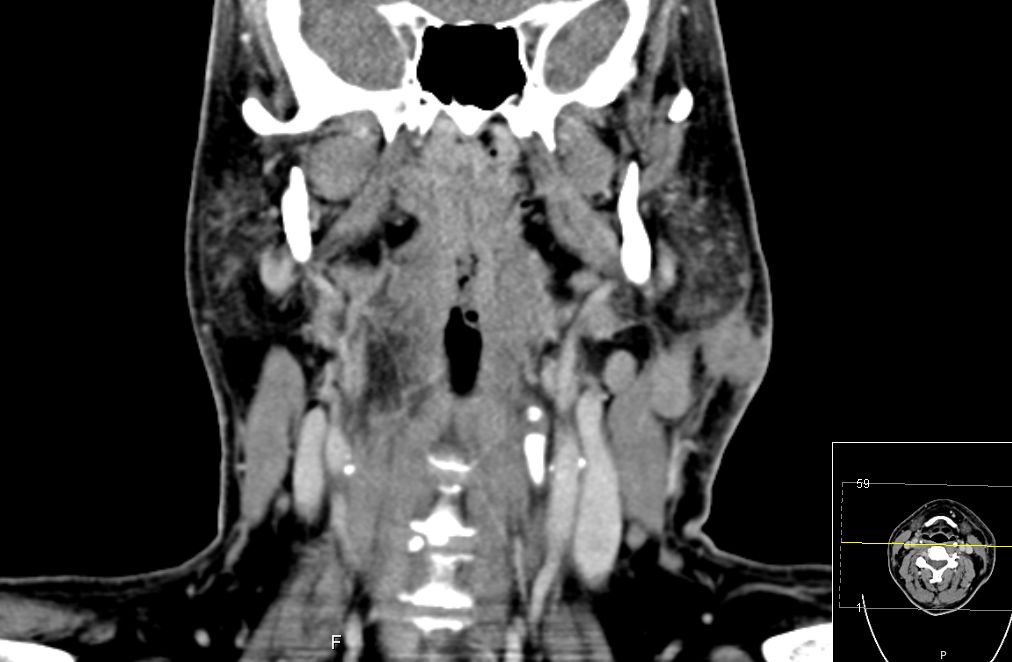

| CT | 51-jähriger Mann, der eine Gesichtsschwellung bemerkte. Adenokarzinom pT3 pN1 Mo L1 G3. Subtotale Protidektomie unter Neuromonitoring, ND LI und II links, Adjuvante RT. ![]() |